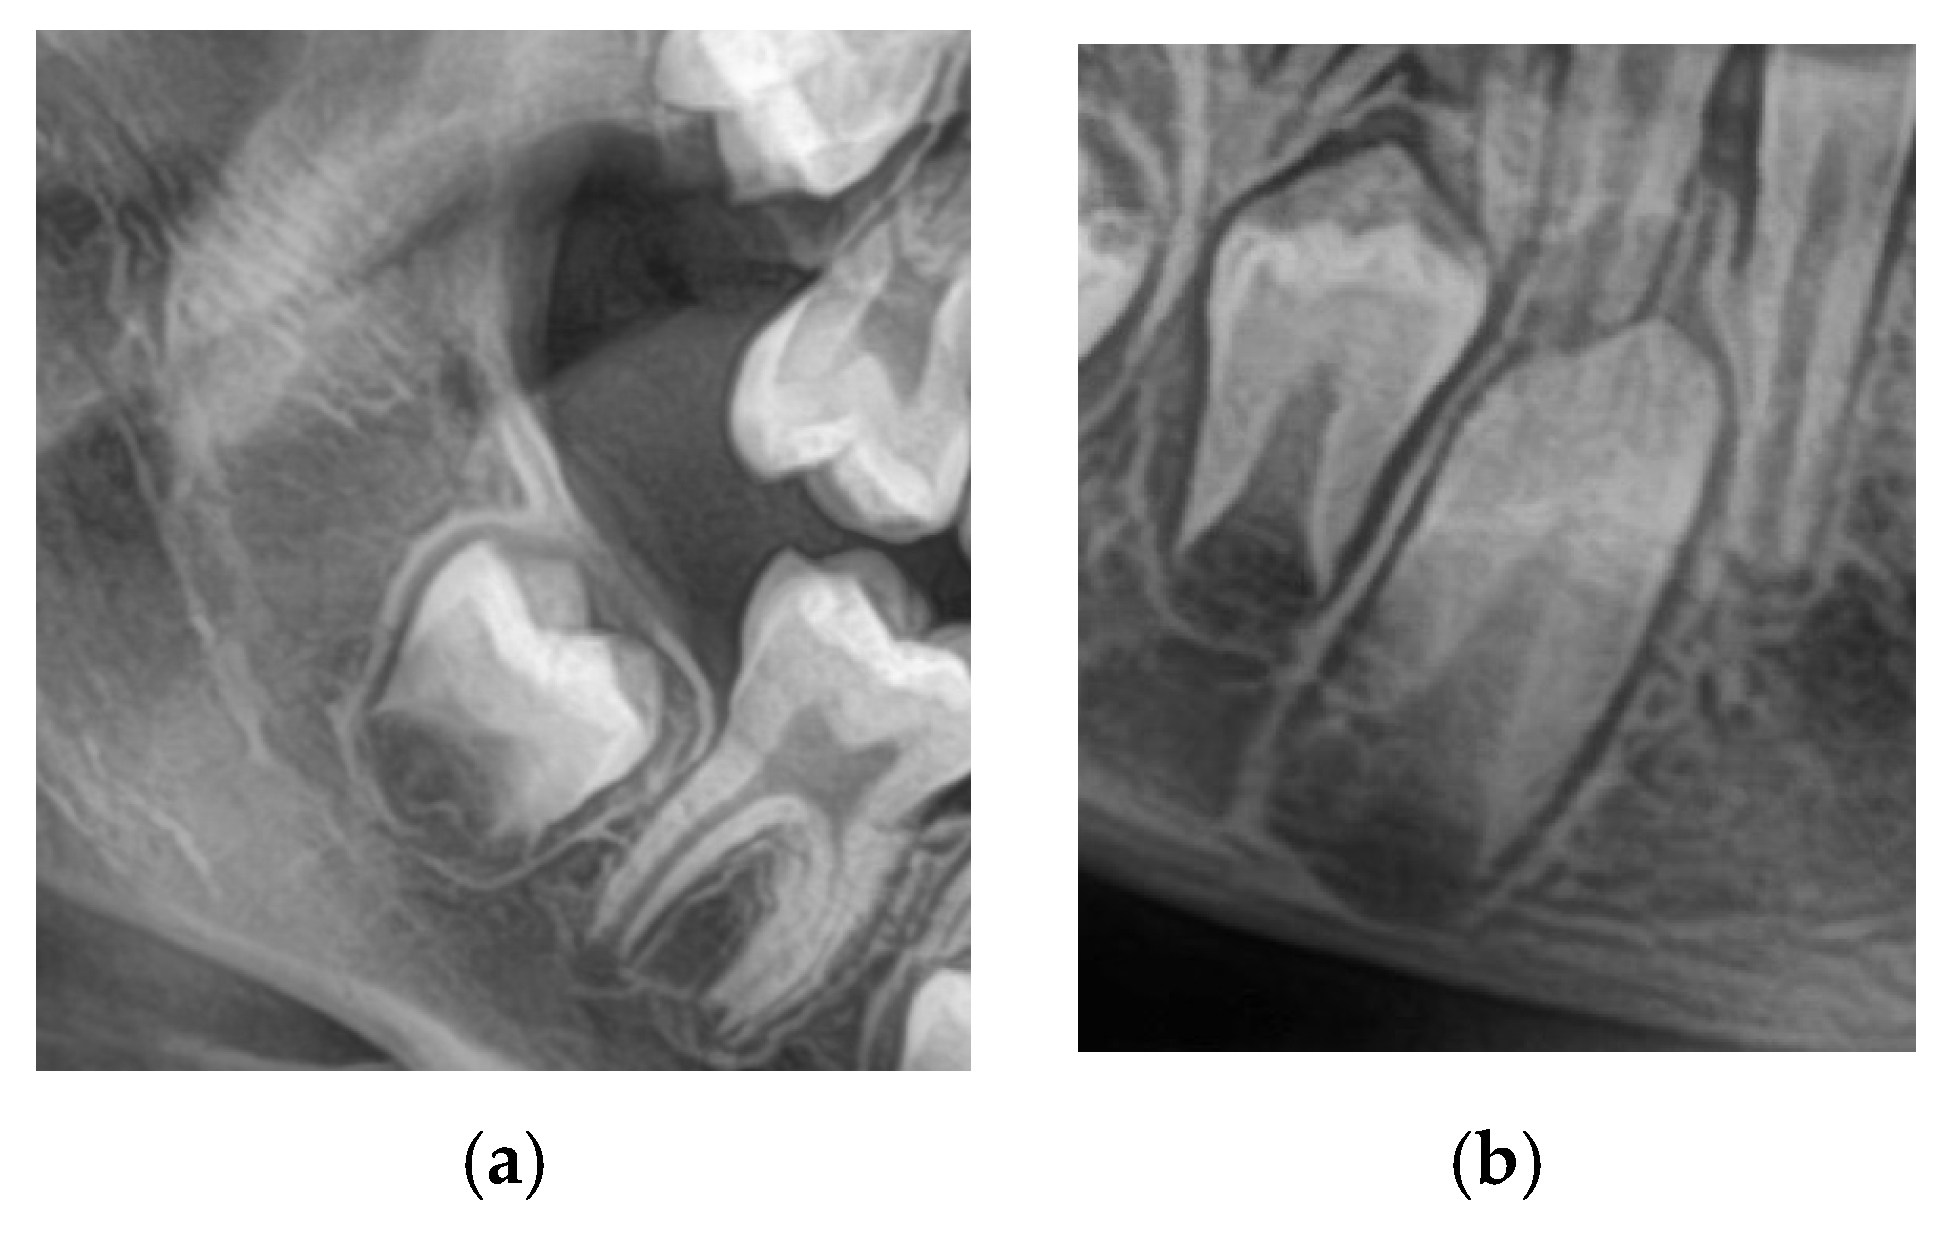

To standardize the assessment and preprocess the images for ML (Machine Learning), each image is individually cropped to isolate the region of interest (ROI) circumscribing the lower second molar and lower canine. Each of these cropped ROIs was saved as a separate image file and named according to the appropriate Demirjian stage. Such a narrowed-down query reduced noise in the form of background data, thereby providing more precise training input to CNN models.

Cohen’s kappa coefficient (κ) was used to assess interrater agreement and ensure the reliability of the annotations. In the event of divergence, the two authors reached a consensus through a joint review. These labeled, cropped images were then used as ground truth, which were in turn used for training and validating the deep learning models. Figure 2 shows the cropped images.

Figure 2.

(a) Cropped lower 2nd Molar. (b) Cropped lower Canine.